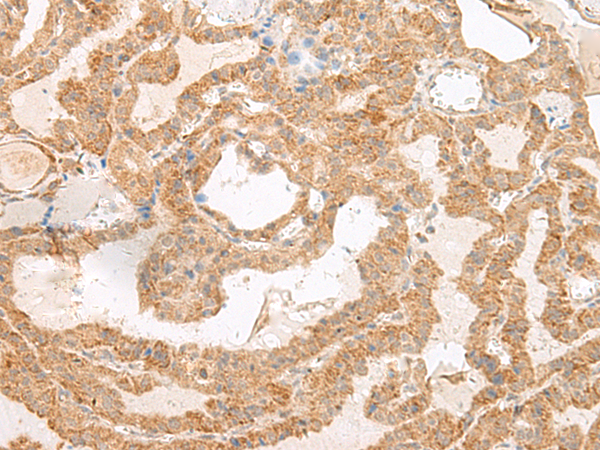

分类: 科研抗体货号: P13453别名: GCET1; SERPINA11; SERPINA11b应用: WB,IHC反应种属: Human